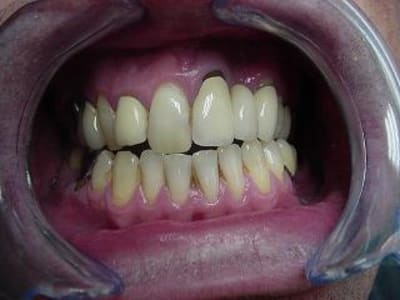

voici un cas paro qui me pose problème: Homme 39 ans, non fumeur, exellente santé ( spotif +++). PAJ dans un mauvais contexte occlusal ( bout à bout et contact essentiellement en posterieur. Je suis un peu paumé sur ce coup là! surtout sur le devenir des molaires. Des pistes avant d'en parler à nice? merci

comme ressace toujours phil, la pano ne suffit pas, il faut un bilan long cone ( ha, ha!). C'est vrai et dans ce cas, on voit très mal une méga poche en M et P de 17. les poches sur 17, 35 et 46 suintent la danette un max...

Enfin pour répondre à steph, je ne pense pas que l'occlusion soit le facteur de cette resorption, car l'atteinte est quant meme partout.

Pour ce qui est de regler l'occlusion, dans un tel cas, comment faire? des meulages sont impossible: trop à supprimer...